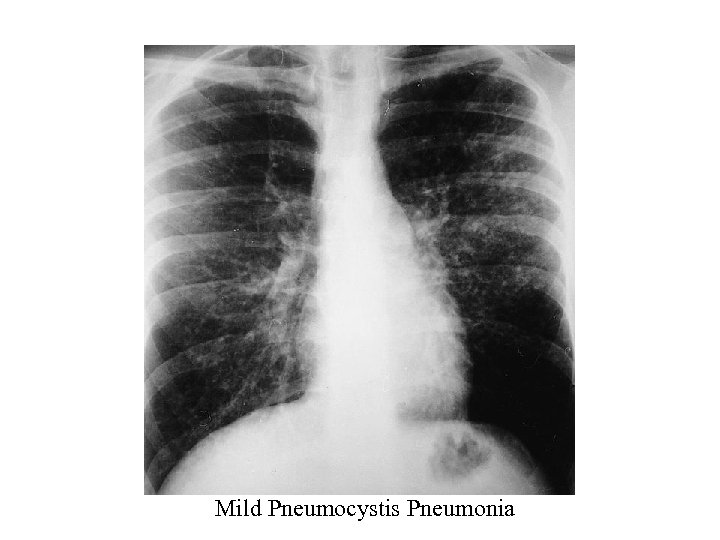

Pneumocystis Pneumonia – CXR typically bilateral interstitial infiltrates or normal (if mild) – Atypical presentations: nodules, blebs and cysts, asymmetric disease, upper lobe localization, and pneumothorax occur. – Pneumothorax in a patient with HIV infection should raise the suspicion of PCP – Cavitation, intrathoracic adenopathy, and pleural effusion are uncommon • presence might indicate an alternative diagnosis. – Approximately 13%– 18% of patients with documented PCP have another concurrent cause of pulmonary dysfunction (e. g. , TB, KS, or bacterial pneumonia) 11

Mild Pneumocystis Pneumonia